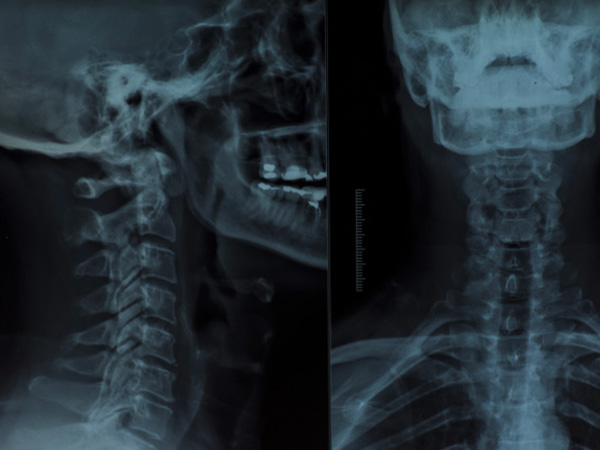

World Radiography Day: Advantages And Disadvantages Of X-rays

Each year on 8 November, World Radiography Day is celebrated to mark the anniversary of the discovery of X-rays by Wilhelm Roentgen in 1895. X-rays are an important imaging tool used to detect bone fractures, some types of injuries, dental problems, certain tumours, foreign objects, etc.

X-rays are a form of electromagnetic radiation that can pass through most objects, including the body. Medically, it is used to generate images of tissues and bone structures inside the body.

When an X-ray beam passes through the body, the tissues and bones absorb the beam in different amounts depending on their density. This generates a shadow that is picked up on a film placed on the opposite side of the X-ray machine.

Radiography, fluoroscopy, and computed tomography (CT) are the types of X-ray imaging used to detect medical conditions. Though X-ray imaging is widely used to help people treat the disease on time, the test has its own share of risks too. Let's find out.